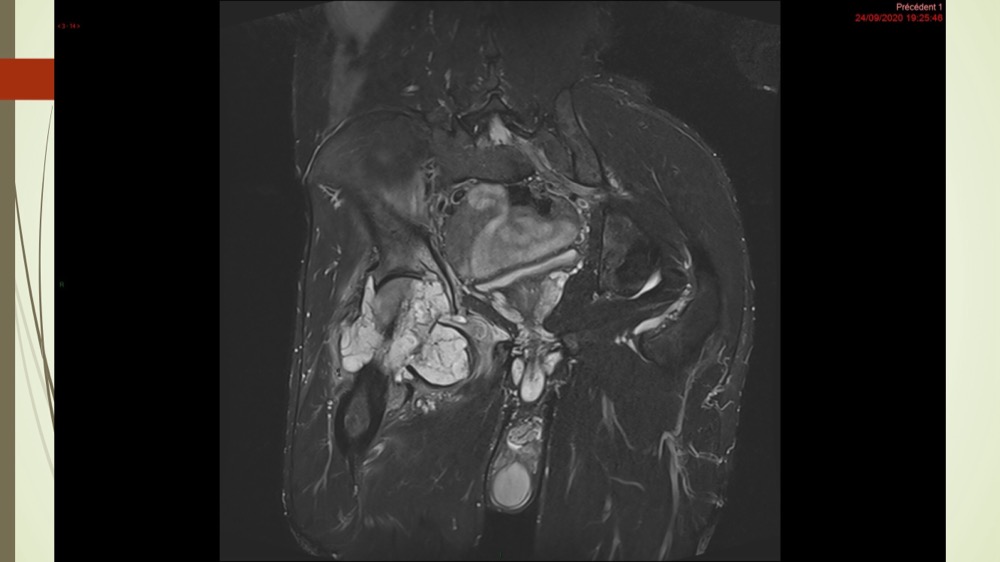

Coxalgie traînante

Kévin Mahé 29/06/2022